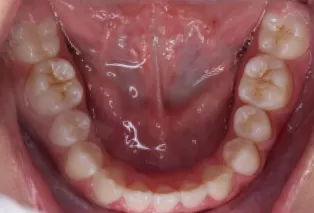

Photos intra-orales après traitement